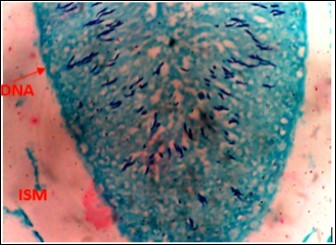

Figure 5.DC+250mg/kg.bw of AP X400 – Section of testis showing scanty DNA deeply stained with magenta color. DNA strands are in clusters

Figure 6.(DC+500mg/kg.bw of AP) X400 – Section of testis showing scanty DNA deeply stained with magenta color. DNA strands are in clusters

From findings in this study, irregular and distorted arrangements of DNA in all diabetic groups (Groups B, C, D, E and F) when compared with the normal control group, may have been due to displacement of sertoli cell within the germinal epithelium of seminiferous tubules. Strands of DNA were also seen arrange in clusters in diabetic groups, showing altered and defective structure which might have resulted from base free side deletion, frame shift, cross-linking and chromosomal rearrangement. The intensity of magenta colour development in Feulgen reaction for DNA demonstration was proportional to DNA concentration. There was reduced colour intensity in all diabetic groups (Groups B, C, D, E and F) when compared with the normal control. This is in line with report from Aitken and Krausz (2001). However the degree of distortion and cross-linking of DNA strand in the group of diabetic animal models placed on high dose (1000mg/kg.bw) of A. polytricha which may be a sign of amelioration. Groups C, D and F placed on 250mg/kg.bw A. polytricha, 500mg/kg.bw A. polytricha and standard anti-diabetic drug (metformin) respectively did not show remarkable differences in terms of DNA arrangements when compared with the diabetic control group. Groups D (500mg/kg.bw A. polytricha) and group E (1000mg/kg.bw) showed visible improvement in magenta colour intensity when compared with the diabetic control group.